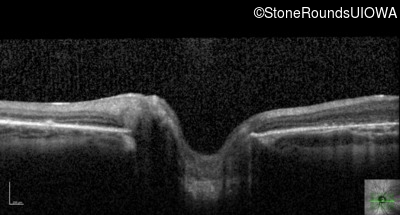

AR Stargardt Disease (IIA)

Age at visit: 6 years

This 6 year old male first experienced a loss of visual acuity at age 5. His acuity was previously normal. He is otherwise healthy.

Diagnosis & molecular findings

Disease Gene Allele 1 variant(s) Allele 2 variant(s) Inheritance mode

AR Stargardt Disease ABCA4 IVS9+1 G>A IVS37+1 G>A AR